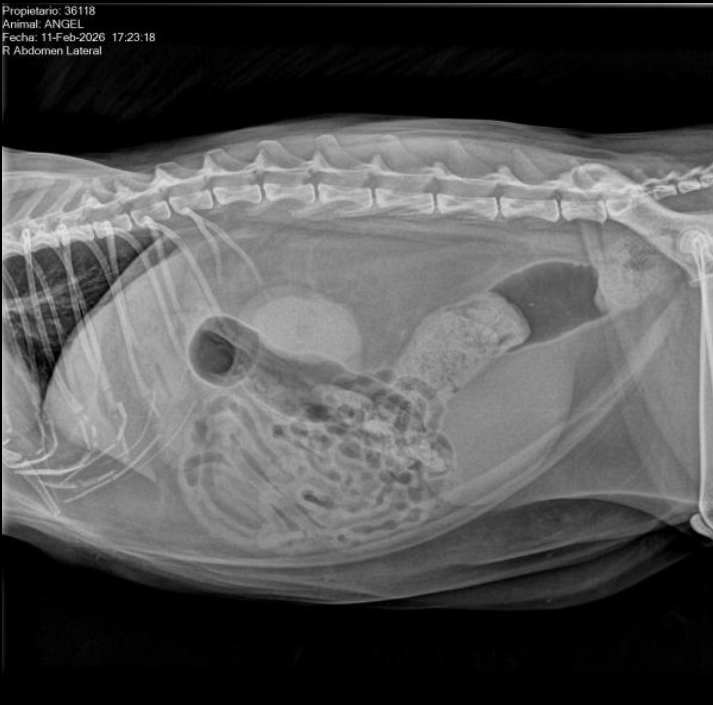

New X-rays showed a large amount of dry stool stuck in his colon and intestines, causing significant abdominal pain. The straining he had to do to pass it is what caused the mucus and blood we saw yesterday morning when we rushed him to the vet hospital. The exact cause of the constipation is still unclear, although it may be related to his kidney failure and dehydration.

This afternoon, he received an enema to help him pass the stool, but follow-up X-rays showed not everything came out, so tomorrow they will perform a second enema.